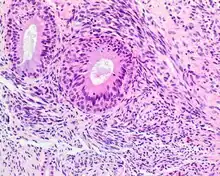

| A high-power view of a hematoxylin- and eosin-stained slide showing respiratory epithelial inclusions within a spindled cell neoplasm showing characteristics of a biphenotypic sinonasal sarcoma | |

- Infiltrative, highly cellular spindled cell neoplasm is poorly circumscribed and unencapsulated. Bone destruction or invasion is common. The cells show medium to long fascicles (nerve fibers), with a herringbone pattern. The cells are remarkably uniform with elongated nuclei. Delicate strands of intercellular collagen without ropy or dense deposition are seen. A very characteristic concurrent surface-type respiratory epithelial proliferation is found from the surface or in small cystic spaces around the cancer cells, often forming glands. The background may have a rich vascularity and usually has a small number of scattered lymphocytes. Extra growths or mitoses are rare, while necrosis, ulceration, and hemorrhage are usually absent.

Smooth-muscle actin reaction in a biphenotypic sinonasal sarcoma - No reactivity occurs with other tumor markers such as SOX10, myogenin, estrogen receptor, progesterone receptor, or keratins.